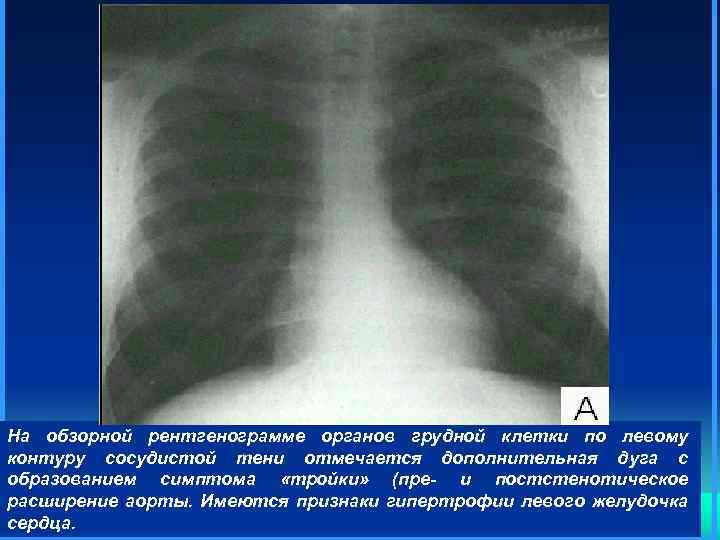

На обзорной рентгенограмме органов грудной клетки по левому контуру сосудистой тени отмечается дополнительная дуга с образованием симптома «тройки» (пре- и постстенотическое расширение аорты. Имеются признаки гипертрофии левого желудочка сердца.

На обзорной рентгенограмме органов грудной клетки по левому контуру сосудистой тени отмечается дополнительная дуга с образованием симптома «тройки» (пре- и постстенотическое расширение аорты. Имеются признаки гипертрофии левого желудочка сердца.